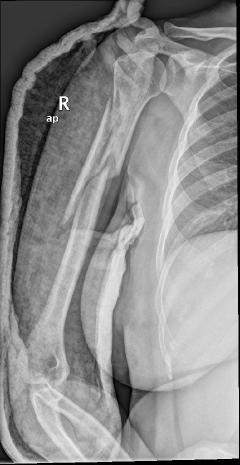

Περίπτωση 3ου ασθενούς

Τα εν λόγω κατάγματα είναι αρκετά συνηθισμένα και συχνά συμβαίνουν μετά από τροχαία ατυχήματα ή πτώση από ύψος. Παρατηρείται εξαιρετικά μεγάλη ποικιλία στη μορφή τους, κατα κανόνα όμως είναι σοβαρά και πολλές φορές ανοικτά – δηλ με τραύμα στο σημείο του κατάγματος – κάτι που αυξάνει τον κίνδυνο λοίμωξης και επιβαρύνει την πορεία της θεραπείας. Στα κατάγματα των άνω άκρων ενδέχεται να υπάρξει και τραυματισμός νεύρων, που χρειάζεται επίσης αντιμετώπιση.

Με τα σύγχρονα μέσα που διαθέτουμε, όλα σχεδόν αυτά τα κατάγματα πρέπει να αντιμετωπίζονται χειρουργικώς. Υπάρχει πληθώρα υλικών οστεοσύνθεσης (πλάκες διαφόρων τύπων, ενδομυελικοί ήλοι, συστήματα εξωτερικής οστεοσύνθεσης) που είναι διαθέσιμα και επαφίεται στην εμπειρία του χειρουργού η επιλογή.

Όλες οι φωτογραφίες ολες προέρχονται από το προσωπικό αρχείο του κου Μ. Τυλλιανάκη